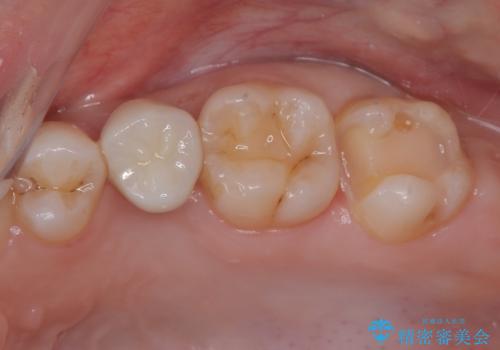

- 左上が虫歯になった気がするとのことで来院された患者様です。

左上の七番目と六番目の歯と歯が接するところに虫歯をレントゲン上で確認できました。

噛み合わせが強く、以前にも当院で右上でゴールドインレーにより治療をされていたのでゴールドインレーにて治療しました。